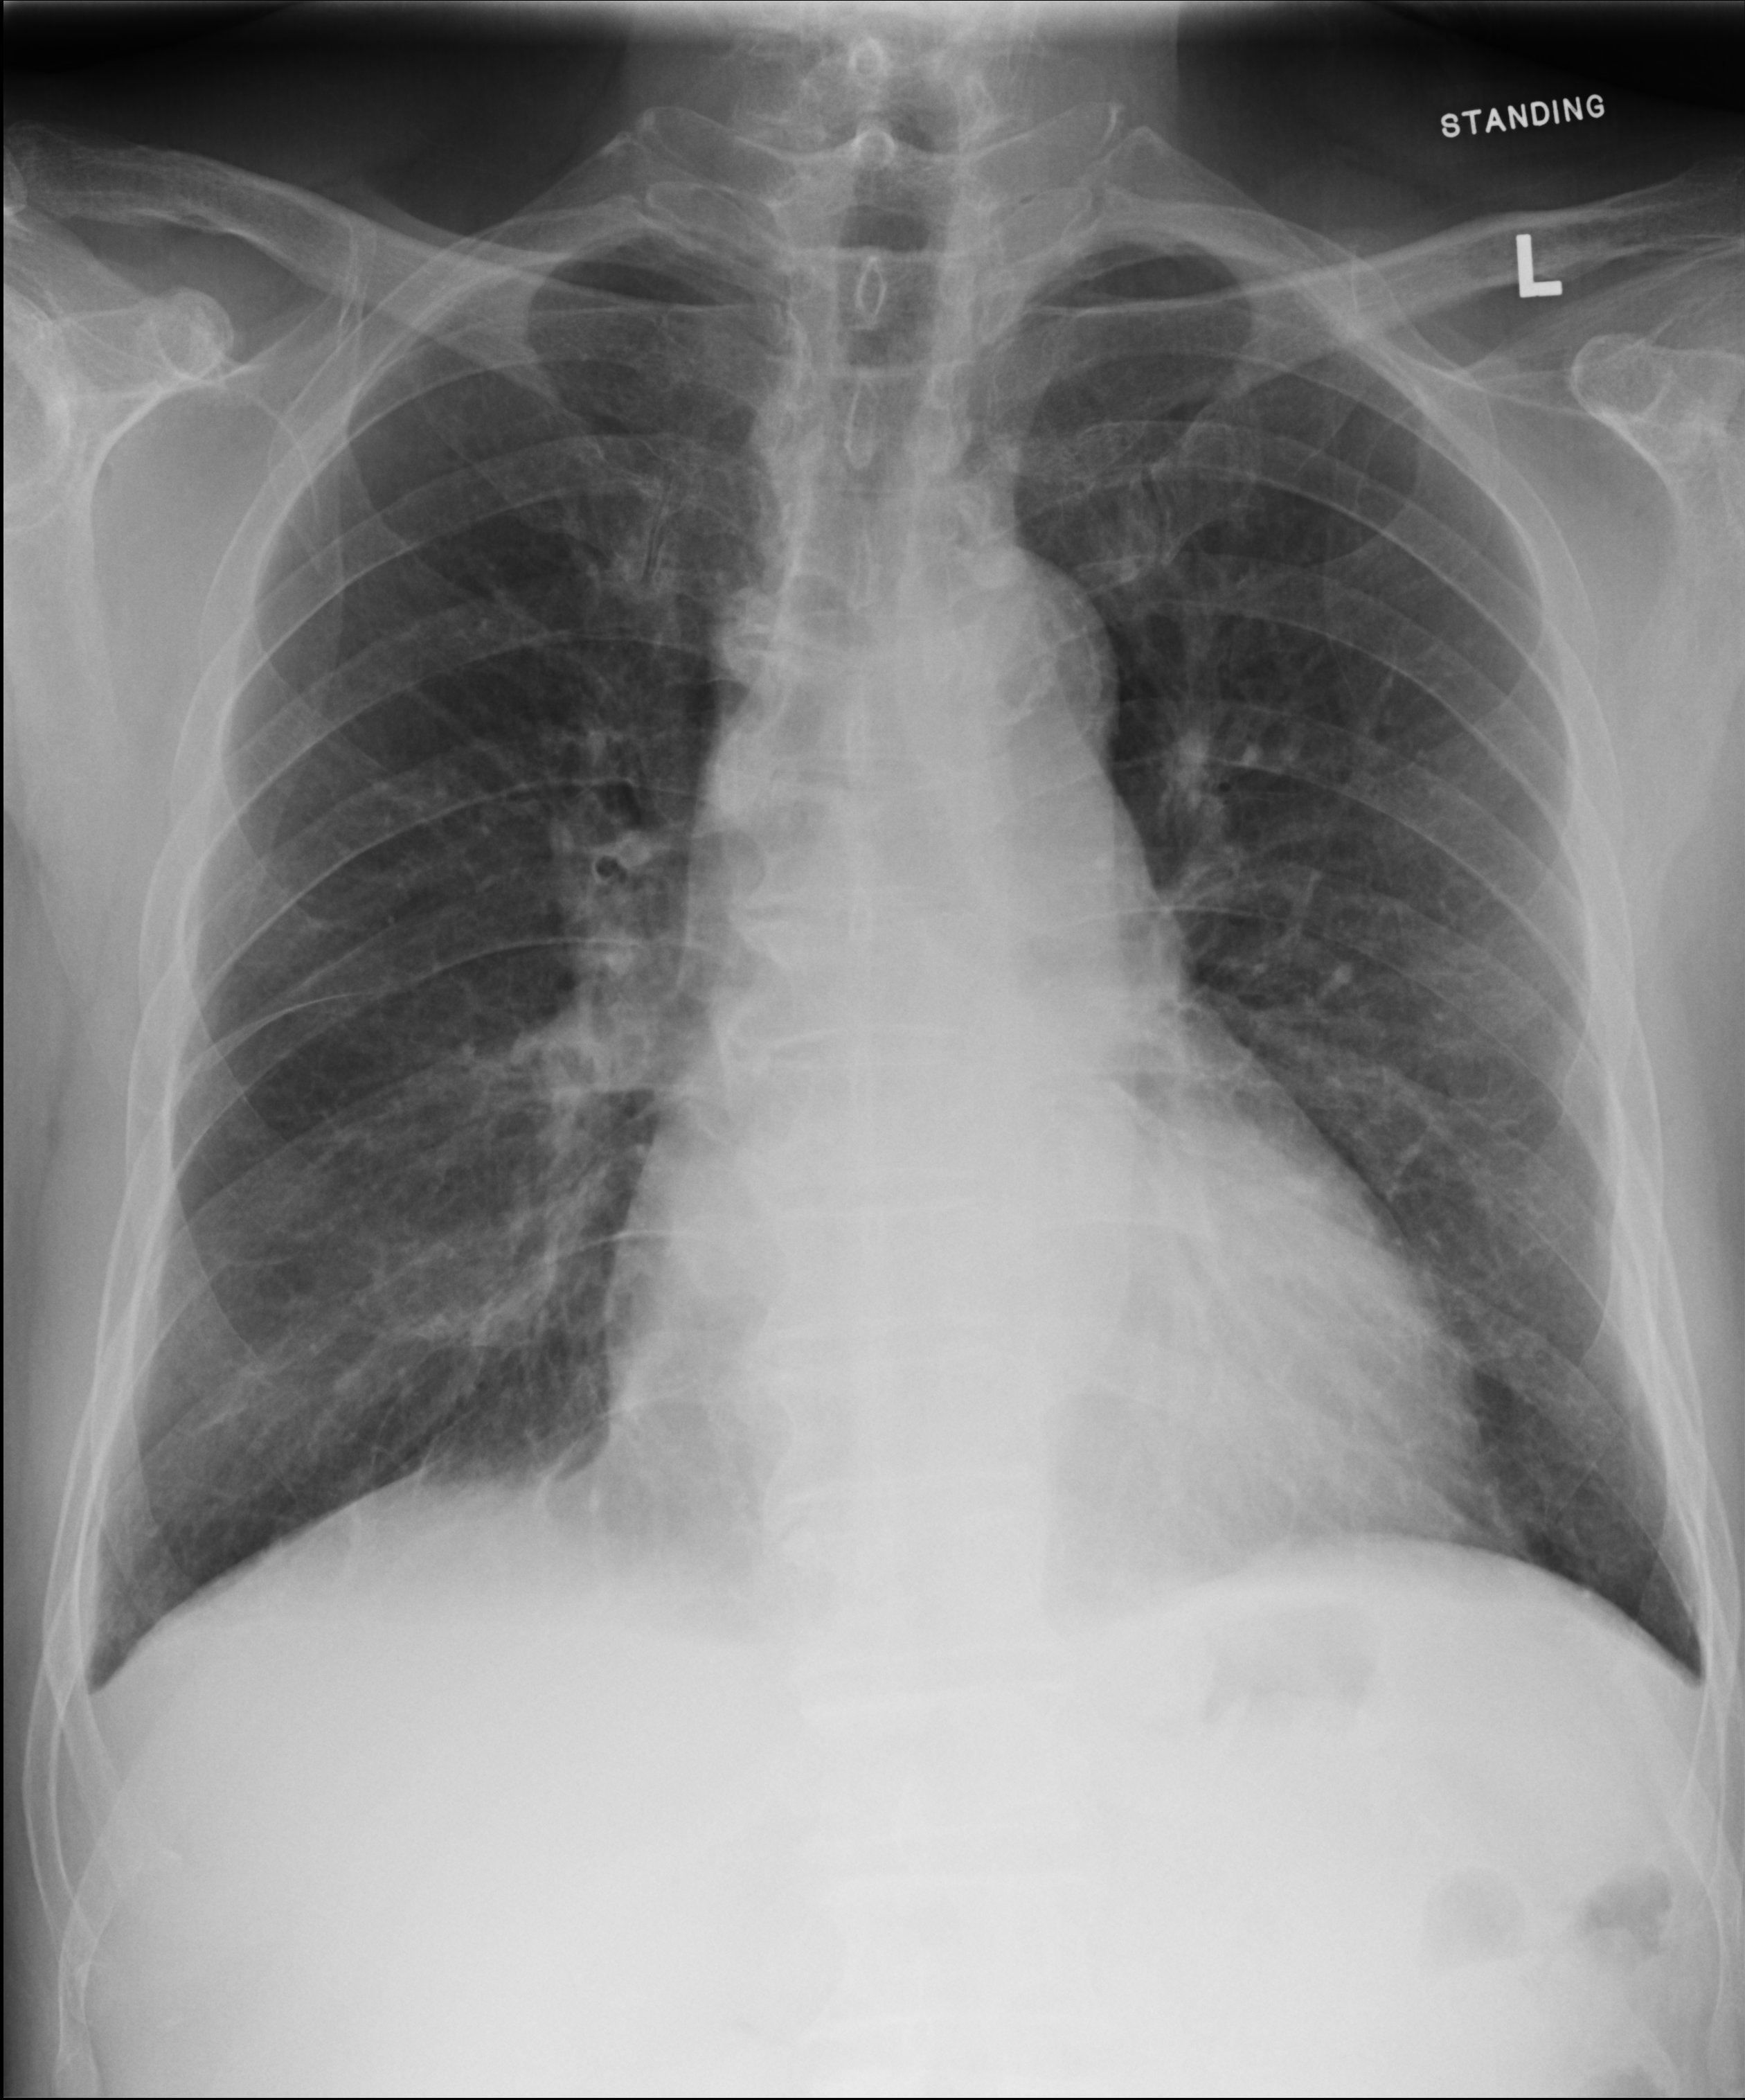

Past Medical History:- Anterior MI/APO with LVEF 35% akinetic LAD territory in Echocardiogram and pLAD occasion with PTCS done in 2018- DM/HT/COPD----------------attend left chest discomfort and SOBEcho showed global LV impairment and LVEF 18% Simpson, no pericardial effusionCTS suggested limited benefit from CABGdecided for multivessel PCI

TnI 54.8<-- 59.1CK 84<- 87ECG SR, Q wave over V1-V3